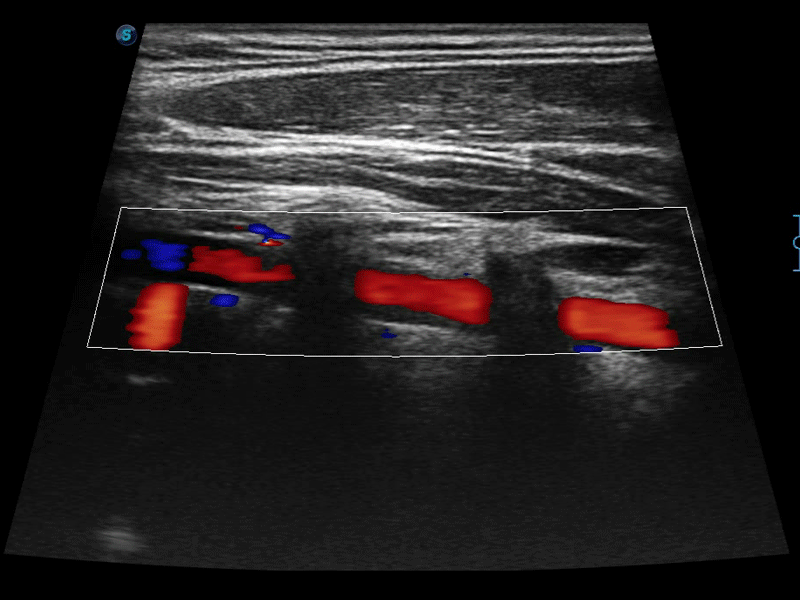

高分辨率血流成像技术提高了对低速血流信号的检测能力。在提高空间分辨率的同时,也克服了血流外溢现象,为用户提供更加真实的血流动力学信息。

自动识别前后壁内膜厚度,为心血管疾病早期评估提供快速准确依据。